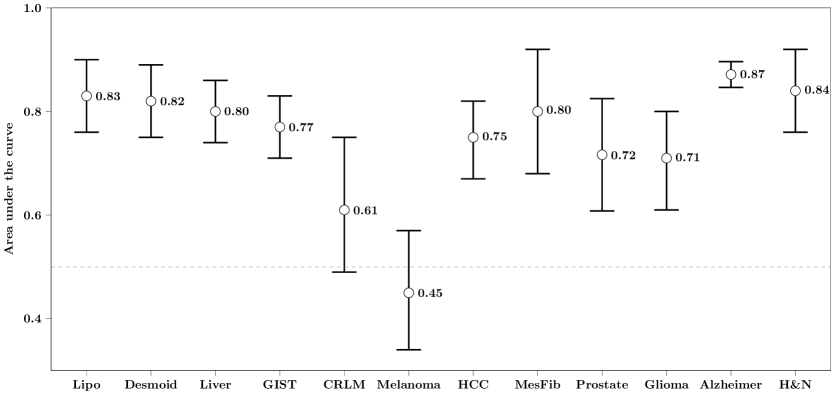

Error plots of the AUC from the application of our WORC framework with the same default configuration on the twelve different datasets are shown in Figure 3; detailed performances, including other metrics, are shown in Table 3; the ROC curves are shown in Figure A.2. In eleven of the twelve datasets, we successfully found a prediction model, with mean AUCs of 0.83 (Lipo), 0.82 (Desmoid), 0.80 (Liver), 0.77 (GIST), 0.61 (CRLM), 0.75 (HCC), 0.80 (MesFib), 0.72 (Prostate), 0.71 (Glioma), 0.87 (Alzheimer), and 0.84 (H&N). In the Melanoma dataset, the mean AUC (0.45) was similar to that of guessing (0.50).